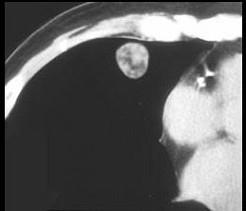

女,71岁,咳嗽,咳痰,胸部隐痛2月余,请结合影像学检查图,选出最可能的诊断 ( )A、结节病B、肺转移瘤C、肺结核D、肺错构瘤E、肺癌

问题 女,71岁,咳嗽,咳痰,胸部隐痛2月余,请结合影像学检查图,选出最可能的诊断 ( )

选项 A、结节病 B、肺转移瘤 C、肺结核 D、肺错构瘤 E、肺癌

答案 D